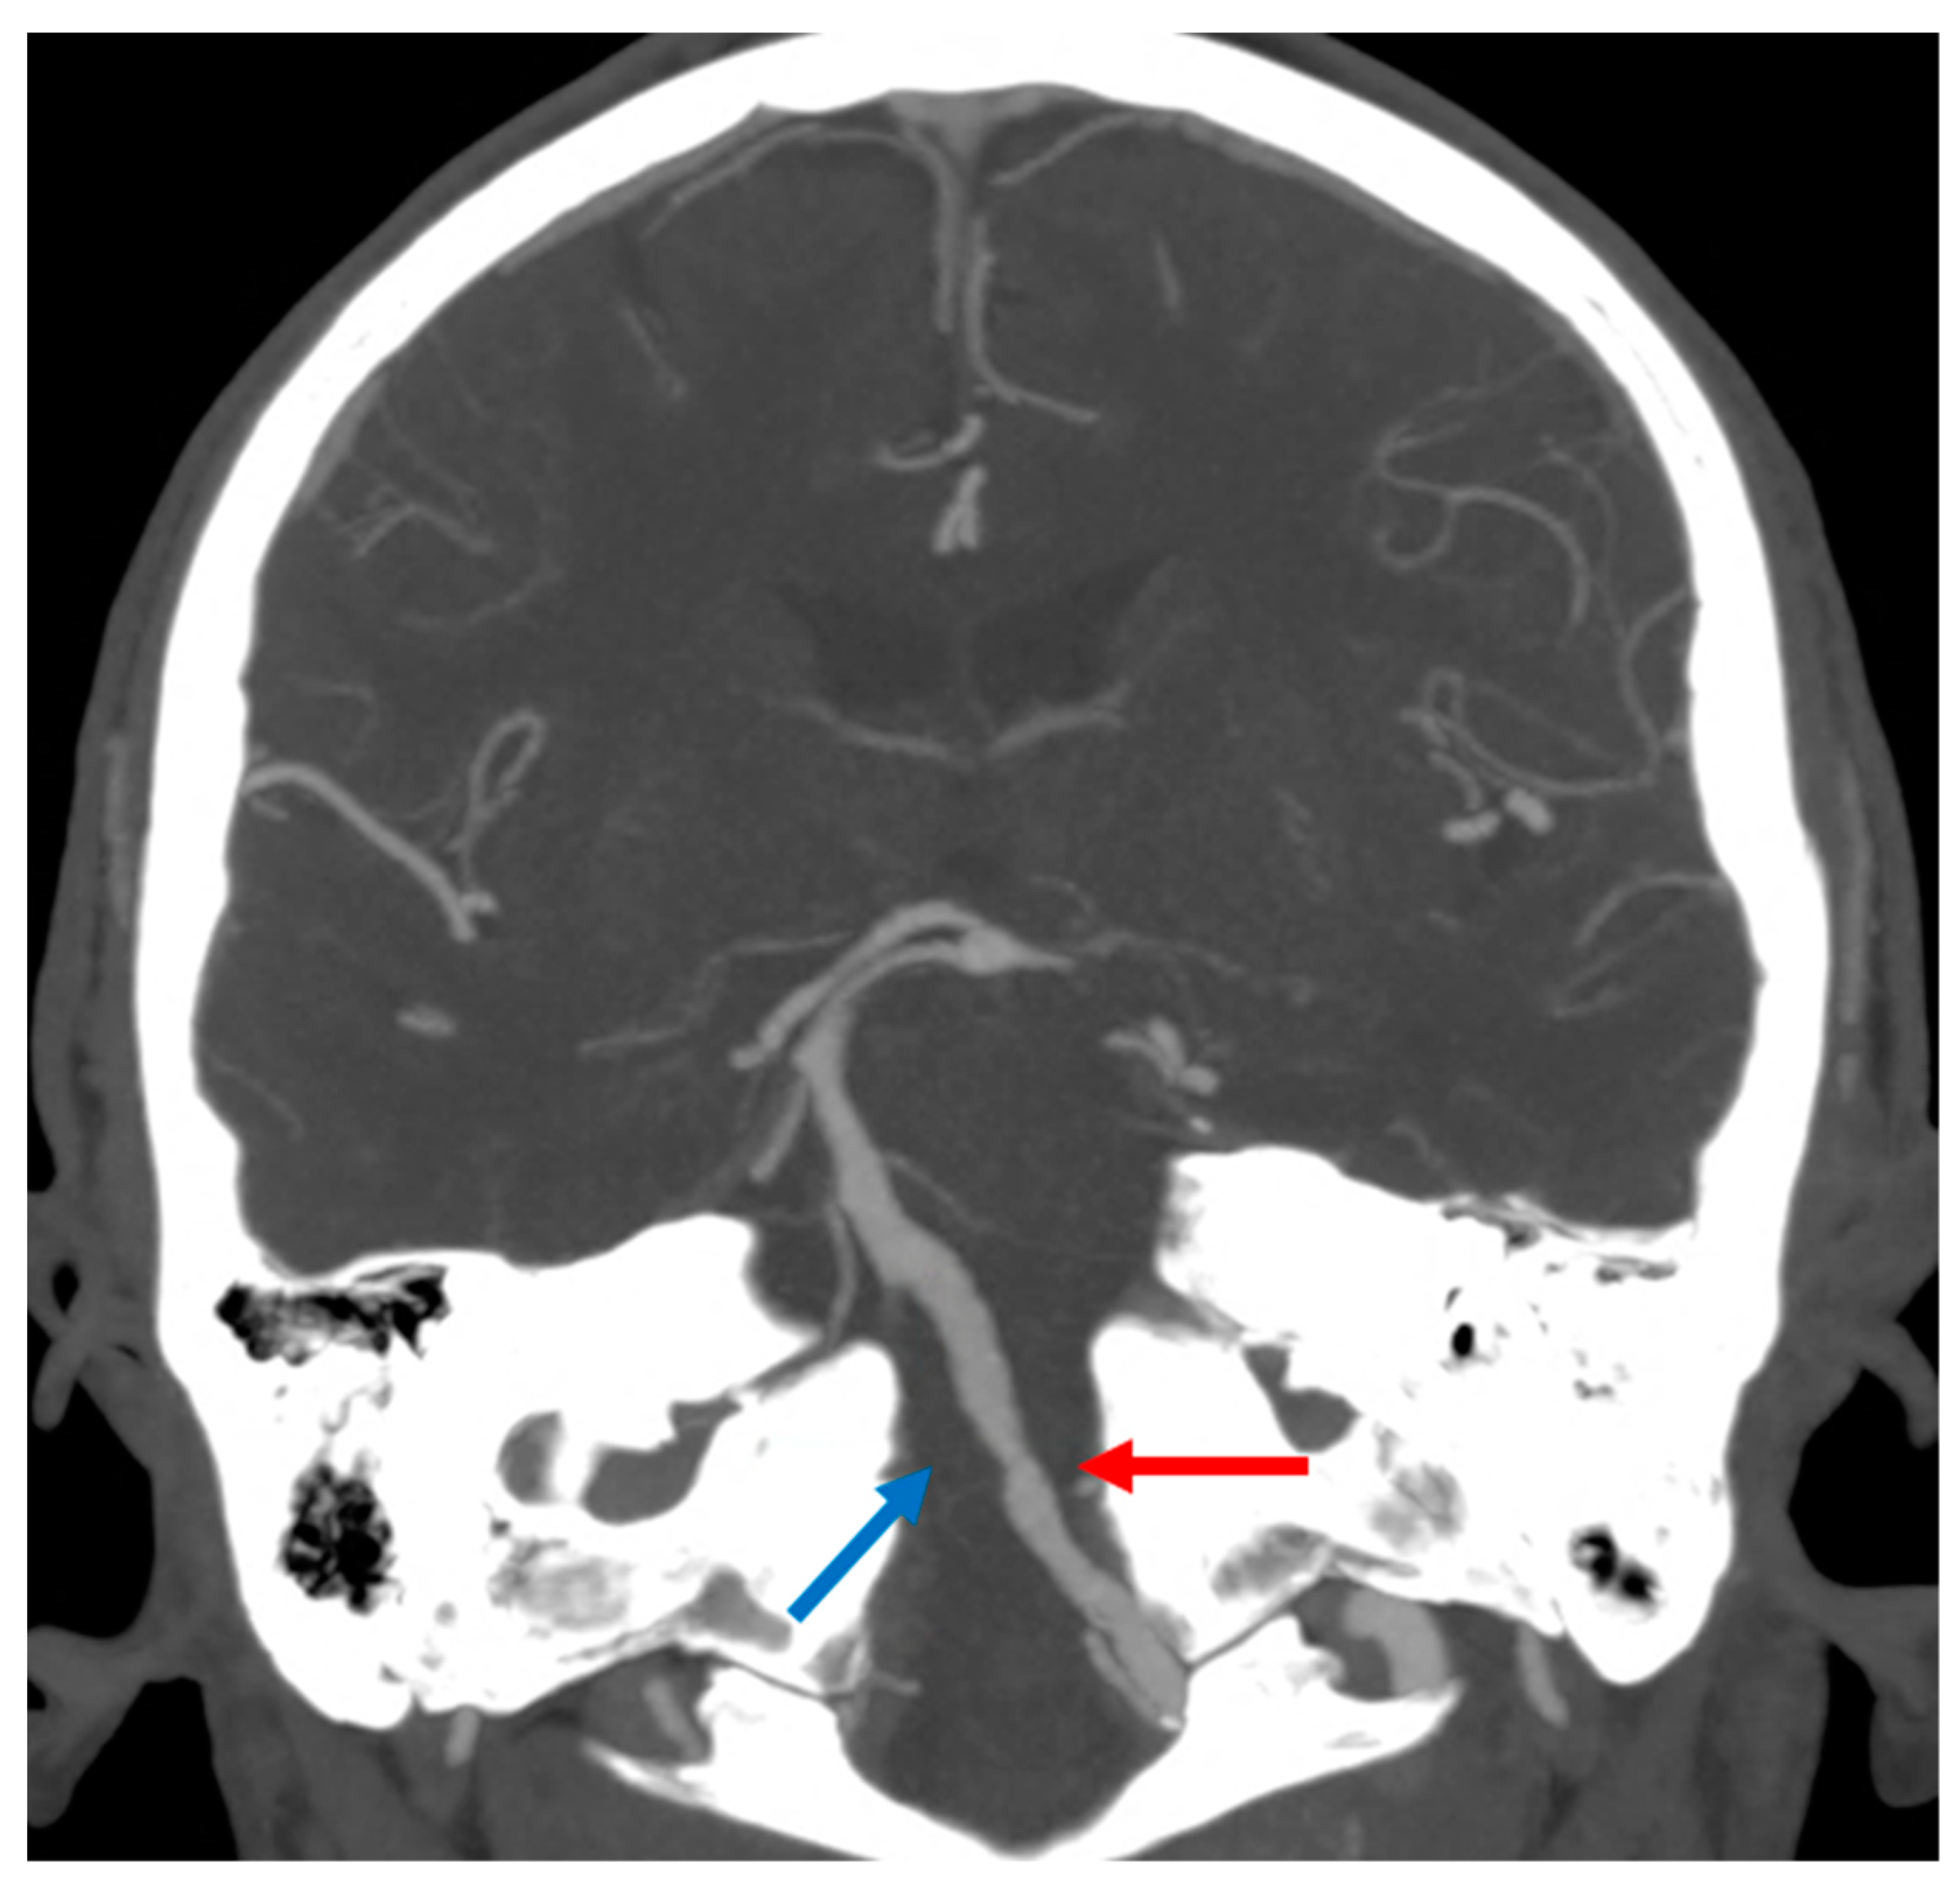

3.2. Pontine Infarction

- Oh, S.; Bang, O.Y.; Chung, C.S.; Lee, K.H.; Chang, W.H.; Kim, G.M. Topographic Location of Acute Pontine Infarction Is Associated with the Development of Progressive Motor Deficits. Stroke 2012, 43, 708–713. [Google Scholar] [CrossRef]

- Kobayashi, J.; Ohara, T.; Minematsu, K.; Nagatsuka, K.; Toyoda, K. Etiological mechanisms of isolated pontine infarcts based on arterial territory involvement. J. Neurol. Sci. 2014, 339, 113–117. [Google Scholar] [CrossRef]

- Vlašković, T.; Brkić, B.G.; Stević, Z.; Vukićević, M.; Đurović, O.; Kostić, D.; Stanisavljević, N.; Marinković, I.; Kapor, S.; Marinković, S. Anatomic and MRI Bases for Pontine Infarctions with Patients Presentation. J. Stroke Cerebrovasc. Dis. 2022, 31, 106613. [Google Scholar] [CrossRef]

- Kataoka, S.; Hori, A.; Shirakawa, T.; Hirose, G. Paramedian pontine infarction: Neurological/topographical correlation. Stroke 1997, 28, 809–815. [Google Scholar] [CrossRef]